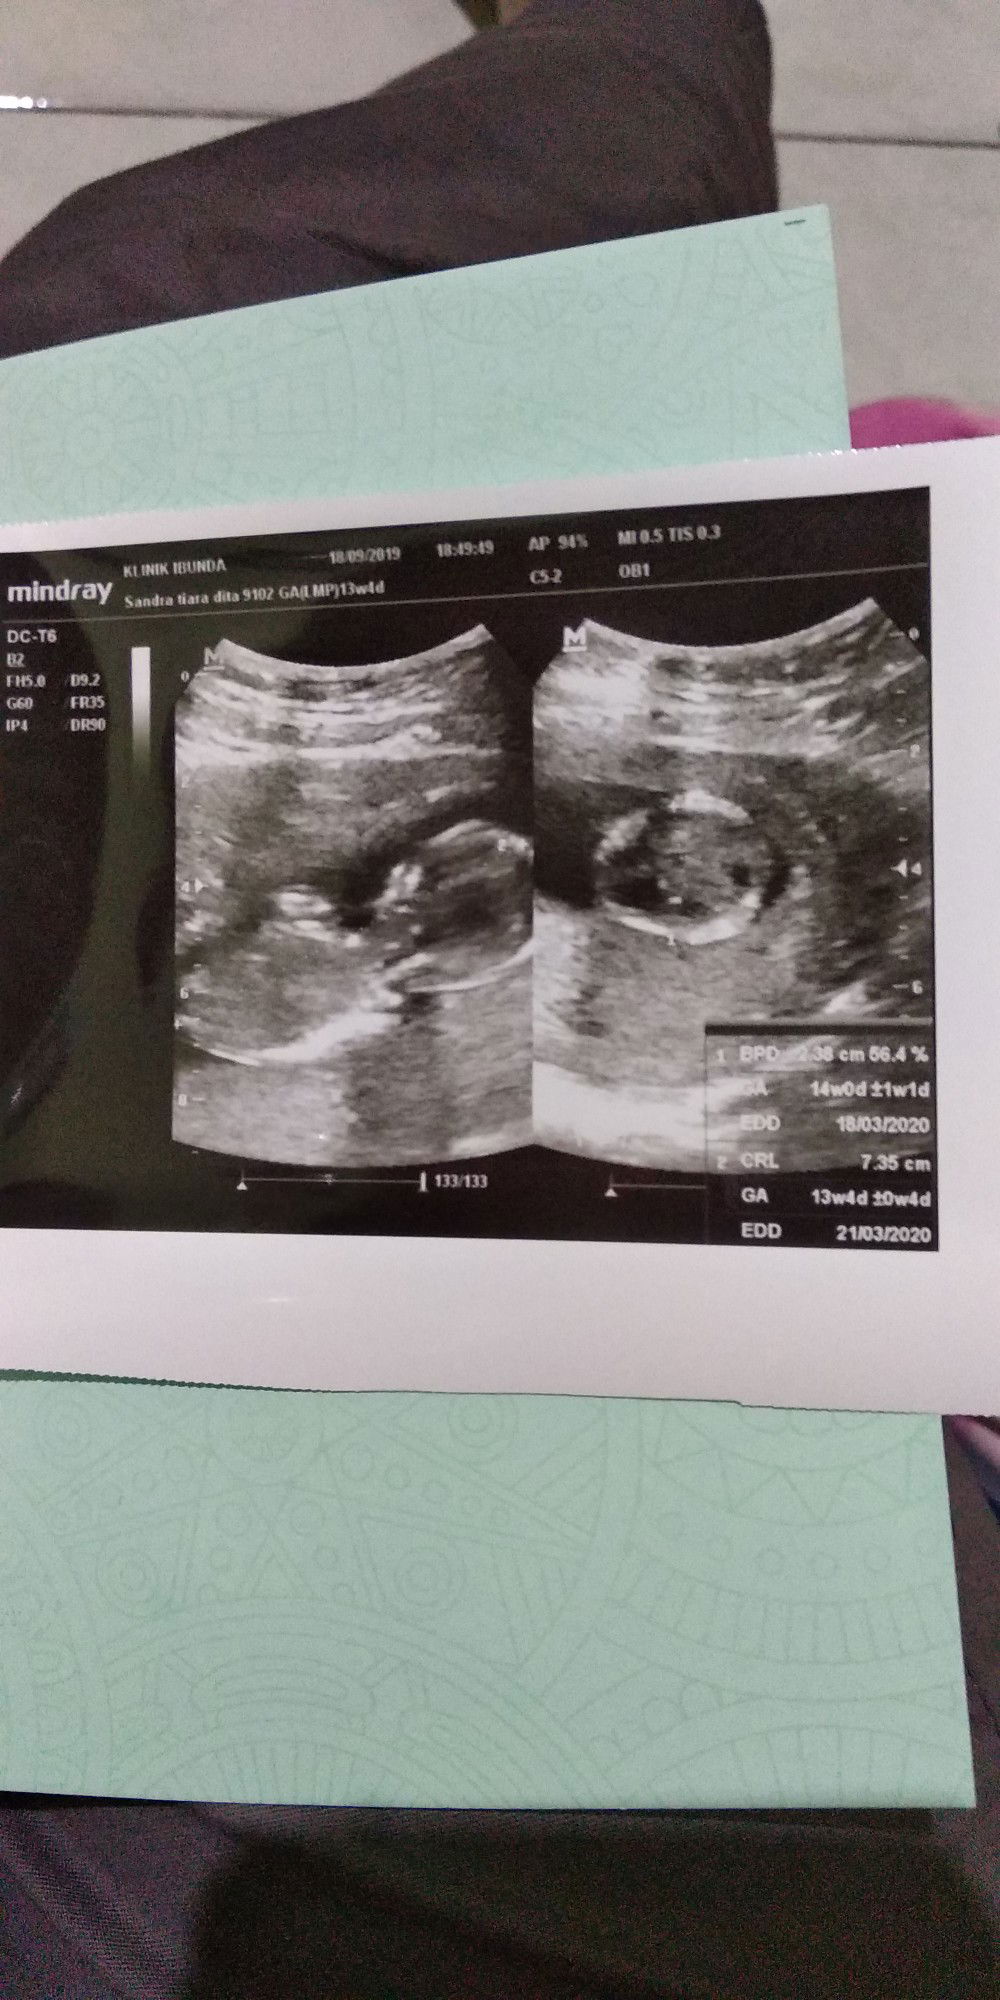

mama with one beautiful girl

apakah ini grow spurt?